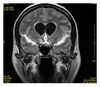

Examples of T1-weighted, T2-weighted and PD-weighted MRI scans

Each tissue returns to its equilibrium state after excitation by the independent relaxation processes of T1 (spin-lattice; that is, magnetization in the same direction as the static magnetic field) and T2 (spin-spin; transverse to the static magnetic field).

To create a T1-weighted image, magnetization is allowed to recover before measuring the MR signal by changing the repetition time (TR). This image weighting is useful for assessing the cerebral cortex, identifying fatty tissue, characterizing focal liver lesions, and in general, obtaining morphological information, as well as for post-contrast imaging.

To create a T2-weighted image, magnetization is allowed to decay before measuring the MR signal by changing the echo time (TE). This image weighting is useful for detecting edema and inflammation, revealing white matter lesions, and assessing zonal anatomy in the prostate and uterus.